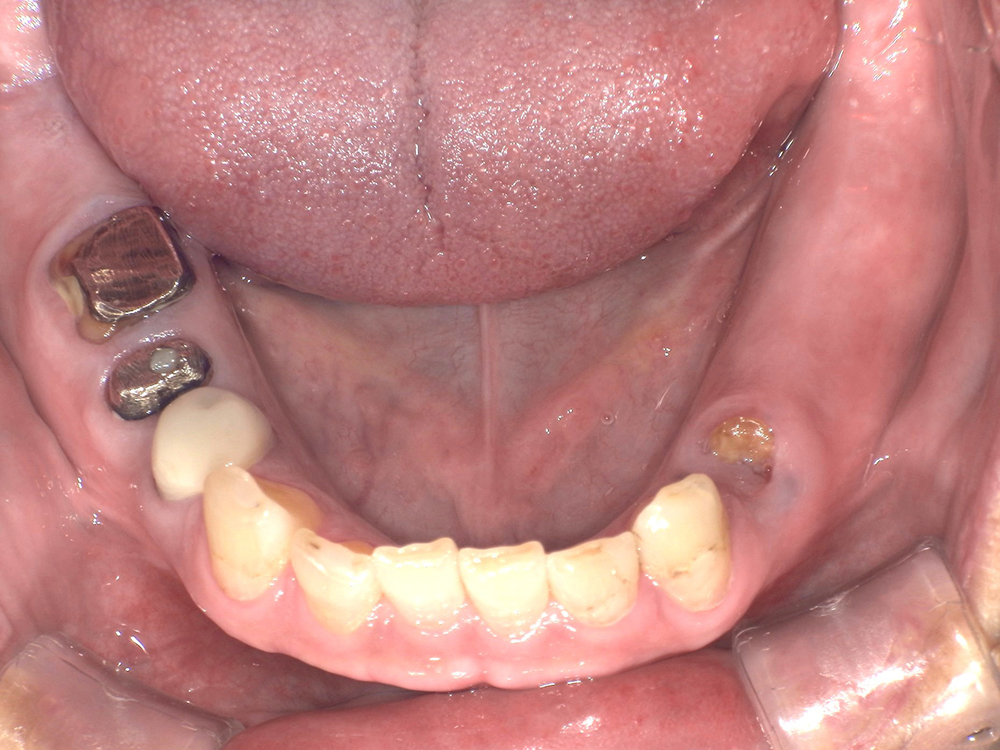

-

<治療前>

<治療後>

主訴:右下奥歯で噛めない 入れ歯は入れたくない

処置内容:ストローマンインプラント2本埋入

骨造成:なし

静脈鎮静:なし

上部構造:フルジルコニア

費用:¥880,000(税込)

治療期間:2カ月

副作用・リスク:

術後の炎症反応により、痛みや腫れが生じますが、およそ1週間ほどで軽快していきます。生活にはほとんど支障がありません。